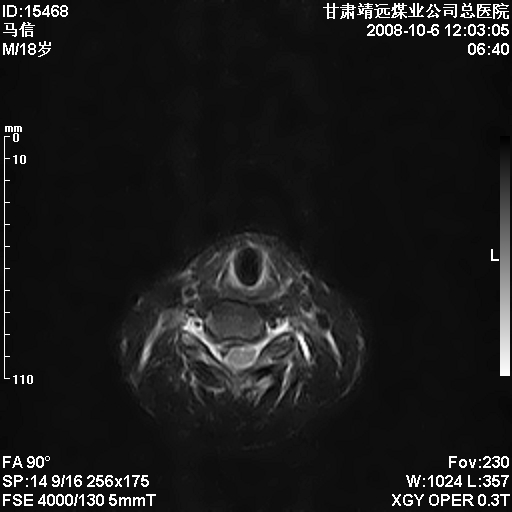

标题: MRI1827:颈椎内异常信号,是不是占位。

患者18岁,学生,在玩耍中受伤来检查,患者喜欢打篮球。颈椎内异常信号影,我们考虑占位,但是不像占位,又考虑硬膜囊的增厚,大家关建看颈椎椎管内的那个异常占位信号

脑脊液流动伪影?

后纵韧带增厚,颈2/3、3/4、4/5、5/6椎间盘变性、突出;椎体有旋转,提示椎小关节有问题;腰椎间盘变性,许莫氏结节。

是正常的脑脊液波动伪影

脑脊液流动伪影

你说的占位是伪影。在我们医院1.5t和3.0t的mr上是经常看见的。